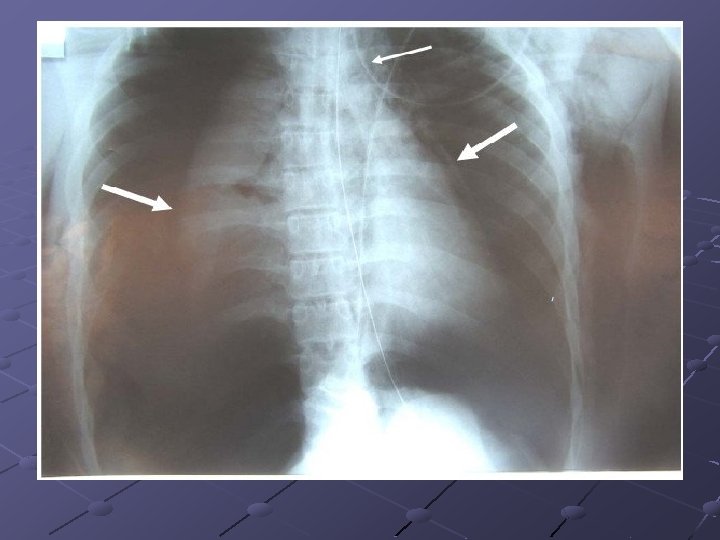

Radiographie du thorax de face, réalisée après la pose pour vérifier la position du drain Si besoin, le médecin repositionne le drain dans les mêmes conditions d’asepsie que lors de la pose Contrôle radiographique après L’IDE note dans le DSI les informations relatives à la pose : Date de pose, Lieu d’implantation, Type de drain (et n°lot) Nom de l’opérateur Difficultés éventuelles Planification du premier pansement Recueil obtenu